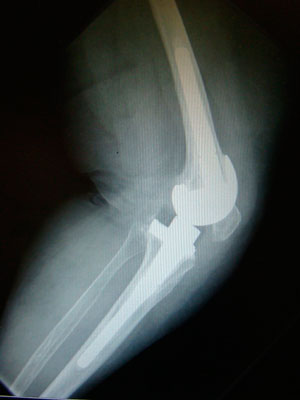

¿Qué hacer si ha fracasado la prótesis de rodilla?

Si la causa es la infección de la prótesis de rodilla, el especialista, con la ayuda de un equipo multidisciplinar, establecerá el mejor tratamiento posible, en un tiempo o en dos tiempos quirúrgicos.

Tanto si la causa es infecciosa como si la causa es la inestabilidad o la pérdida ósea, o el aflojamiento mecánico, no infeccioso, el cirujano buscará restaurar la biomecánica de la articulación, la pérdida de hueso y conseguir colocar una nueva prótesis con una fijación sólida al hueso remanente y que le aporte al paciente una estabilidad inmediata.

Hay diferentes medidas para manejar la pérdida de hueso, como el relleno de cemento (para defectos de hasta 3 mm), el uso de cuñas o aumentos metálicos (hasta un máximo de 15 mm de pérdida de hueso en el fémur distal y 10 mm en la tibia), la utilización de vástagos modulares de extensión (prolongaciones de la prótesis hacía el canal del fémur y de la tibia que consiguen la fijación y reparto de las cargas en una zona más sana), el uso de injerto óseo, o la mejora en la fijación en la metáfisis mediante vainas o conos metafisarios de metal ultraporoso que favorecen la incorporación del injerto óseo y la fijación de la prótesis.

El cirujano ha de buscar la prótesis con menor grado de constricción posible que aporte estabilidad.

En general utilizaremos una prótesis de rodilla tipo bisagra rotatoria en caso de ausencia de ambos ligamentos colaterales, tendencia a la hiperextensión severa, pérdida ósea masiva con ligamentos colaterales insuficientes o no reparables, graves deformidades axiales, o ante una discrepancia severa del espacio articular en flexión y en extensión, que no se puede solucionar mediante aumentos modulares.

Los vástagos cementados presentan como ventajas una mayor versatilidad, con la posibilidad de usarse ante canales deformes, pueden ser más cortos, liberan antibiótico, permiten una fijación inmediata, y los estudios muestran una supervivencia del 94% a los 10 años.

La decisión final dependerá del conocimiento y nivel de experiencia del cirujano, teniendo en cuenta la evidencia científica disponible.

Los vástagos intramedulares cementados permiten repartir las cargas en un área de hueso más grande, evitando el fracaso de las prótesis de revisión. El uso de cemento con 1-2 antibióticos permitirá prevenir nuevas complicaciones, como en las prótesis primarias de rodilla.